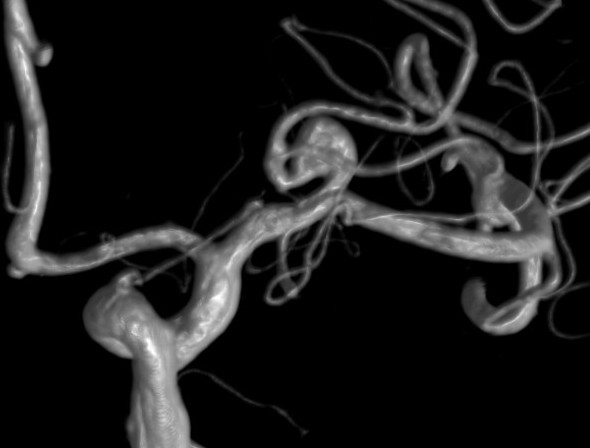

We are proud in Turku University Hospital Finland to be the first in Europe to treat intracranial aneurysms with the redesign Pipeline Vantage flow diverter together with RIST radial access system. Already two patients treated with this excellent combination.